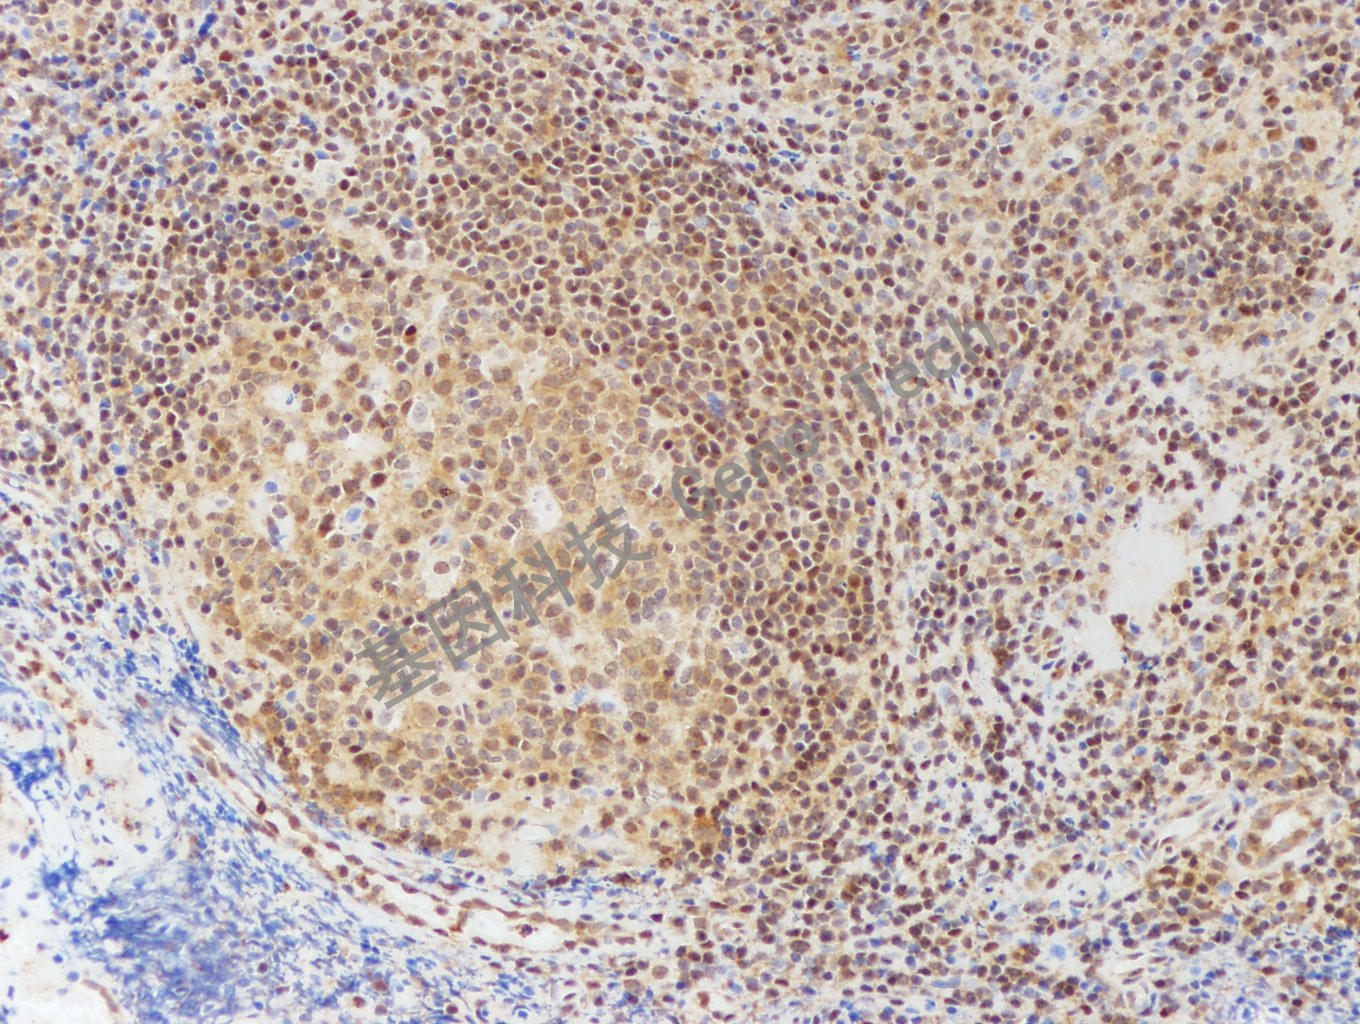

| 扁桃體石蠟切片,用 DPC4(GT2080)染色,細(xì)胞漿/細(xì)胞核陽性,DAB 顯色。 | ||

| 預(yù)處理:高pH熱修復(fù) | 陽性部位:細(xì)胞漿/細(xì)胞核 | 陽性對(duì)照:小腸 |

| 簡介:DPC4基因,又稱SMAD4基因,是一種抑癌基因,最初從胰腺癌中發(fā)現(xiàn),位于染色體18q21.1上,參與調(diào)控TGF-β信號(hào)通路,DPC4功能失活或表達(dá)低下可能影響TGF-β的信號(hào)轉(zhuǎn)導(dǎo)并參與腫瘤的形成。研究發(fā)現(xiàn)近50%胰腺導(dǎo)管腺癌有該基因的突變或缺失,DPC4缺失表達(dá)常發(fā)生于腫瘤進(jìn)展晚期。此外多種腫瘤亦可發(fā)生DPC4的突變或缺失,如急性髓性白血病、卵巢癌、結(jié)腸癌和乳腺癌等。 | ||